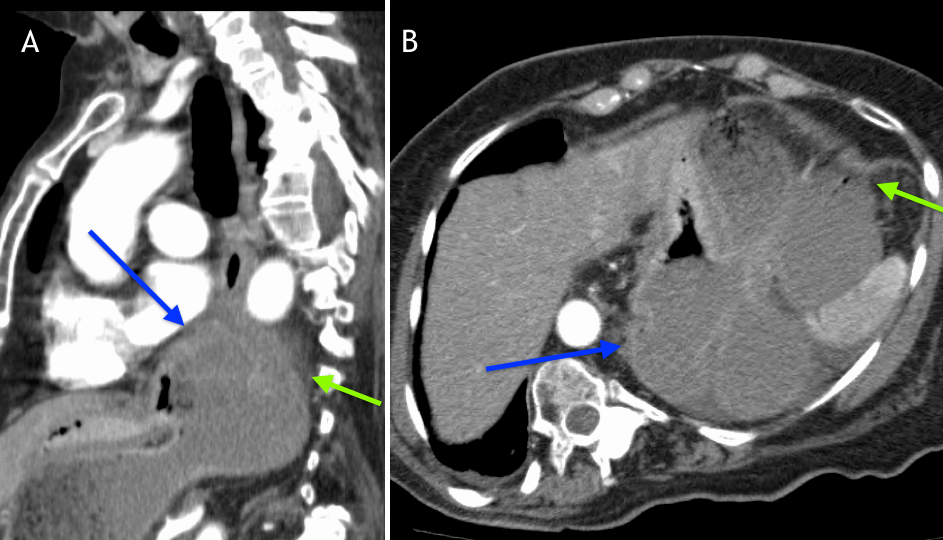

Gastric volvulus associated with agenesis of the left lobe of the liver Gastric Volvulus Radiographics Gastric rotation and volvulus may occur in an organoaxial plane (along the long axis of the stomach) or in the mesenteroaxial plane. Gastric volvulus is a rare entity with a spectrum of acute and chronic clinical presentations. Abdominal pain, nausea, and vomiting are common presenting symptoms among adult patients seeking care in the. It can be both an emergency and. Gastric Volvulus Radiographics.